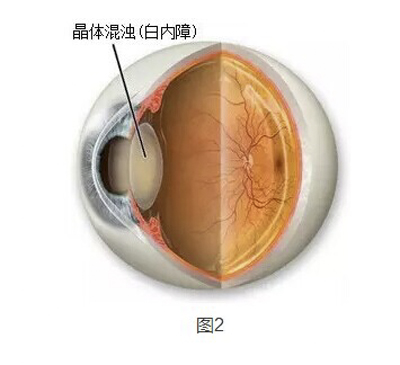

A:飛蠅症又稱飛蚊症和玻璃體混濁,是指玻璃體內出現不透明體,造成患者視物出現模糊。人出生時玻璃體呈凝膠狀態,是重要的屈光介質,正常的玻璃體隨著年齡逐漸出現液化,從而導致玻璃體混濁。此外,一切玻璃體混濁是由於病理原因所導致,例如玻璃體出血、葡萄……

A:眼前出現飛蚊的症狀往往是因為玻璃體發生了液化、變性和混濁,通常情況下玻璃體的混濁,比較多見於近視眼的人和年歲比較大的中老年人,還要特別重視的一個問題是當眼底有病變發生的時候,也會出現玻璃體的混濁、玻璃體混濁的加重,這時候眼前飛蚊的症狀需要做……

A:眼睛裡有飛蚊的現象主要是因為玻璃體發生了液化、變性和混濁,玻璃體原本在眼睛裡邊是一個膠凍狀的結構,由於近視眼以及中高度近視或者年齡過大了,中老年人就會出現玻璃體的液化、變性和混濁,這種情況下很難通過任何治療,將已經液化的玻璃體恢復到膠凍狀的……